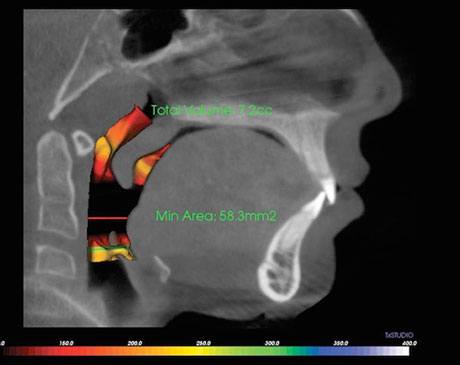

Snoring is the number one sign of sleep apnea. Sleep apnea is a condition where there are breaks or pauses in your breathing while you sleep. It is caused by the soft tissues in your palate or throat relaxing into your airways when you sleep, as well as the general narrowness of the airways and other similar abnormalities. Obstructions are often caused by the soft palate relaxing and descending into the throat during sleep. They are also common in people who are overweight or who have a short or thick throat. Oversized tonsils and adenoids can also cause the obstruction. In many cases, the obstruction is not visible when looking into the patient’s mouth or by feeling their throat, so the detailed images provided by Dr. Shokri and her 3D imaging technology are much more effective at identifying any obstructions to diagnose sleep apnea and determine the best course of treatment.Other signs of the condition include daytime tiredness, weight-gain, difficulty concentrating, and moodiness.

Dr. Shokri is unique in her holistic approach to dental healthcare. Her use of state of the art technology like the Galileo 3D scanner allows her to identify the root cause of the obstructive sleep apnea and provide the most effective in-office or at home treatment available. If you snore, wake often during the night, suffer from daytime drowsiness, weight gain, or moodiness, seek an assessment. The health risks associated with sleep apnea are serious but avoidable with proper treatment.